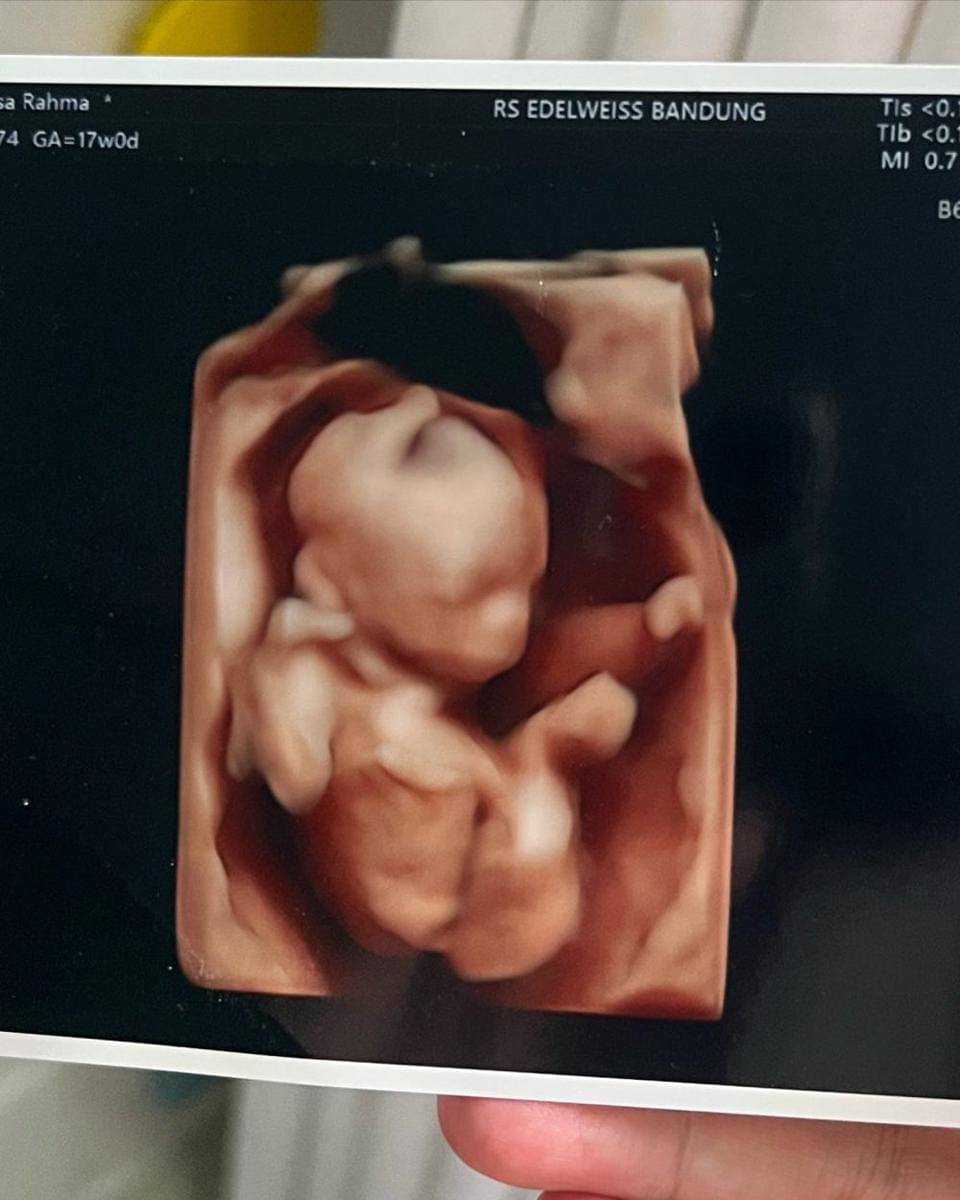

4. Saat ini, usia kehamilan Anisa sudah memasuki 17 minggu. Struktur tubuh calon buah hatinya pun mulai terbentuk